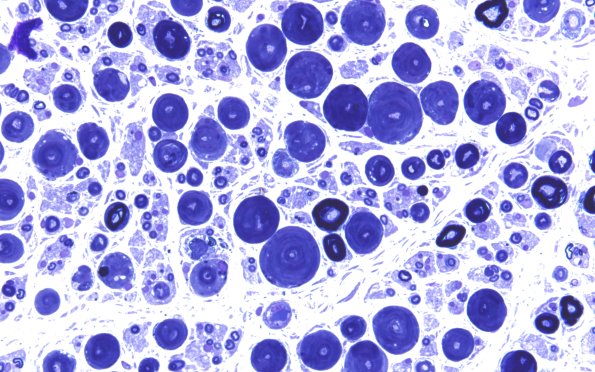

Washington University Experience | PERIPHERAL NEUROPATHY | 0 PNS ARTIFACTS | 18F1 Artifact, vesicular myelin Plastic 2A

18F1,2 Additional examples of vesicular myelin artifact. (Toluidine blue stained one micron thick plastic embedded sections)